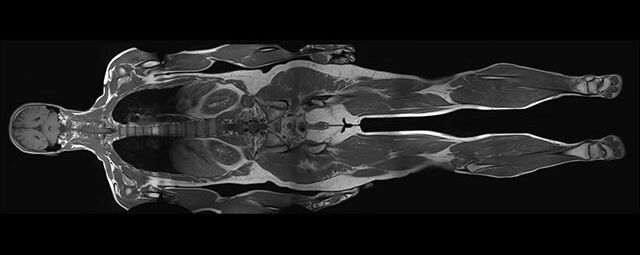

Ganzkörper Angiographie mit Kontrastmittel

• MR-Angiographie mit Kontrastmittel

• Erfassung arterieller und venöser Gefäße/Bypässe aller Körperregionen mit 3D-Rekonstruktion

• je nach klinischer Fragestellung zeitaufgelöste MR-Angiographie (4D-MRA) z.B. bei Frage arteriovenöse Fistel/ Shunt oder Darstellung Unterschenkelarterien vor geplanter Bypassoperation.